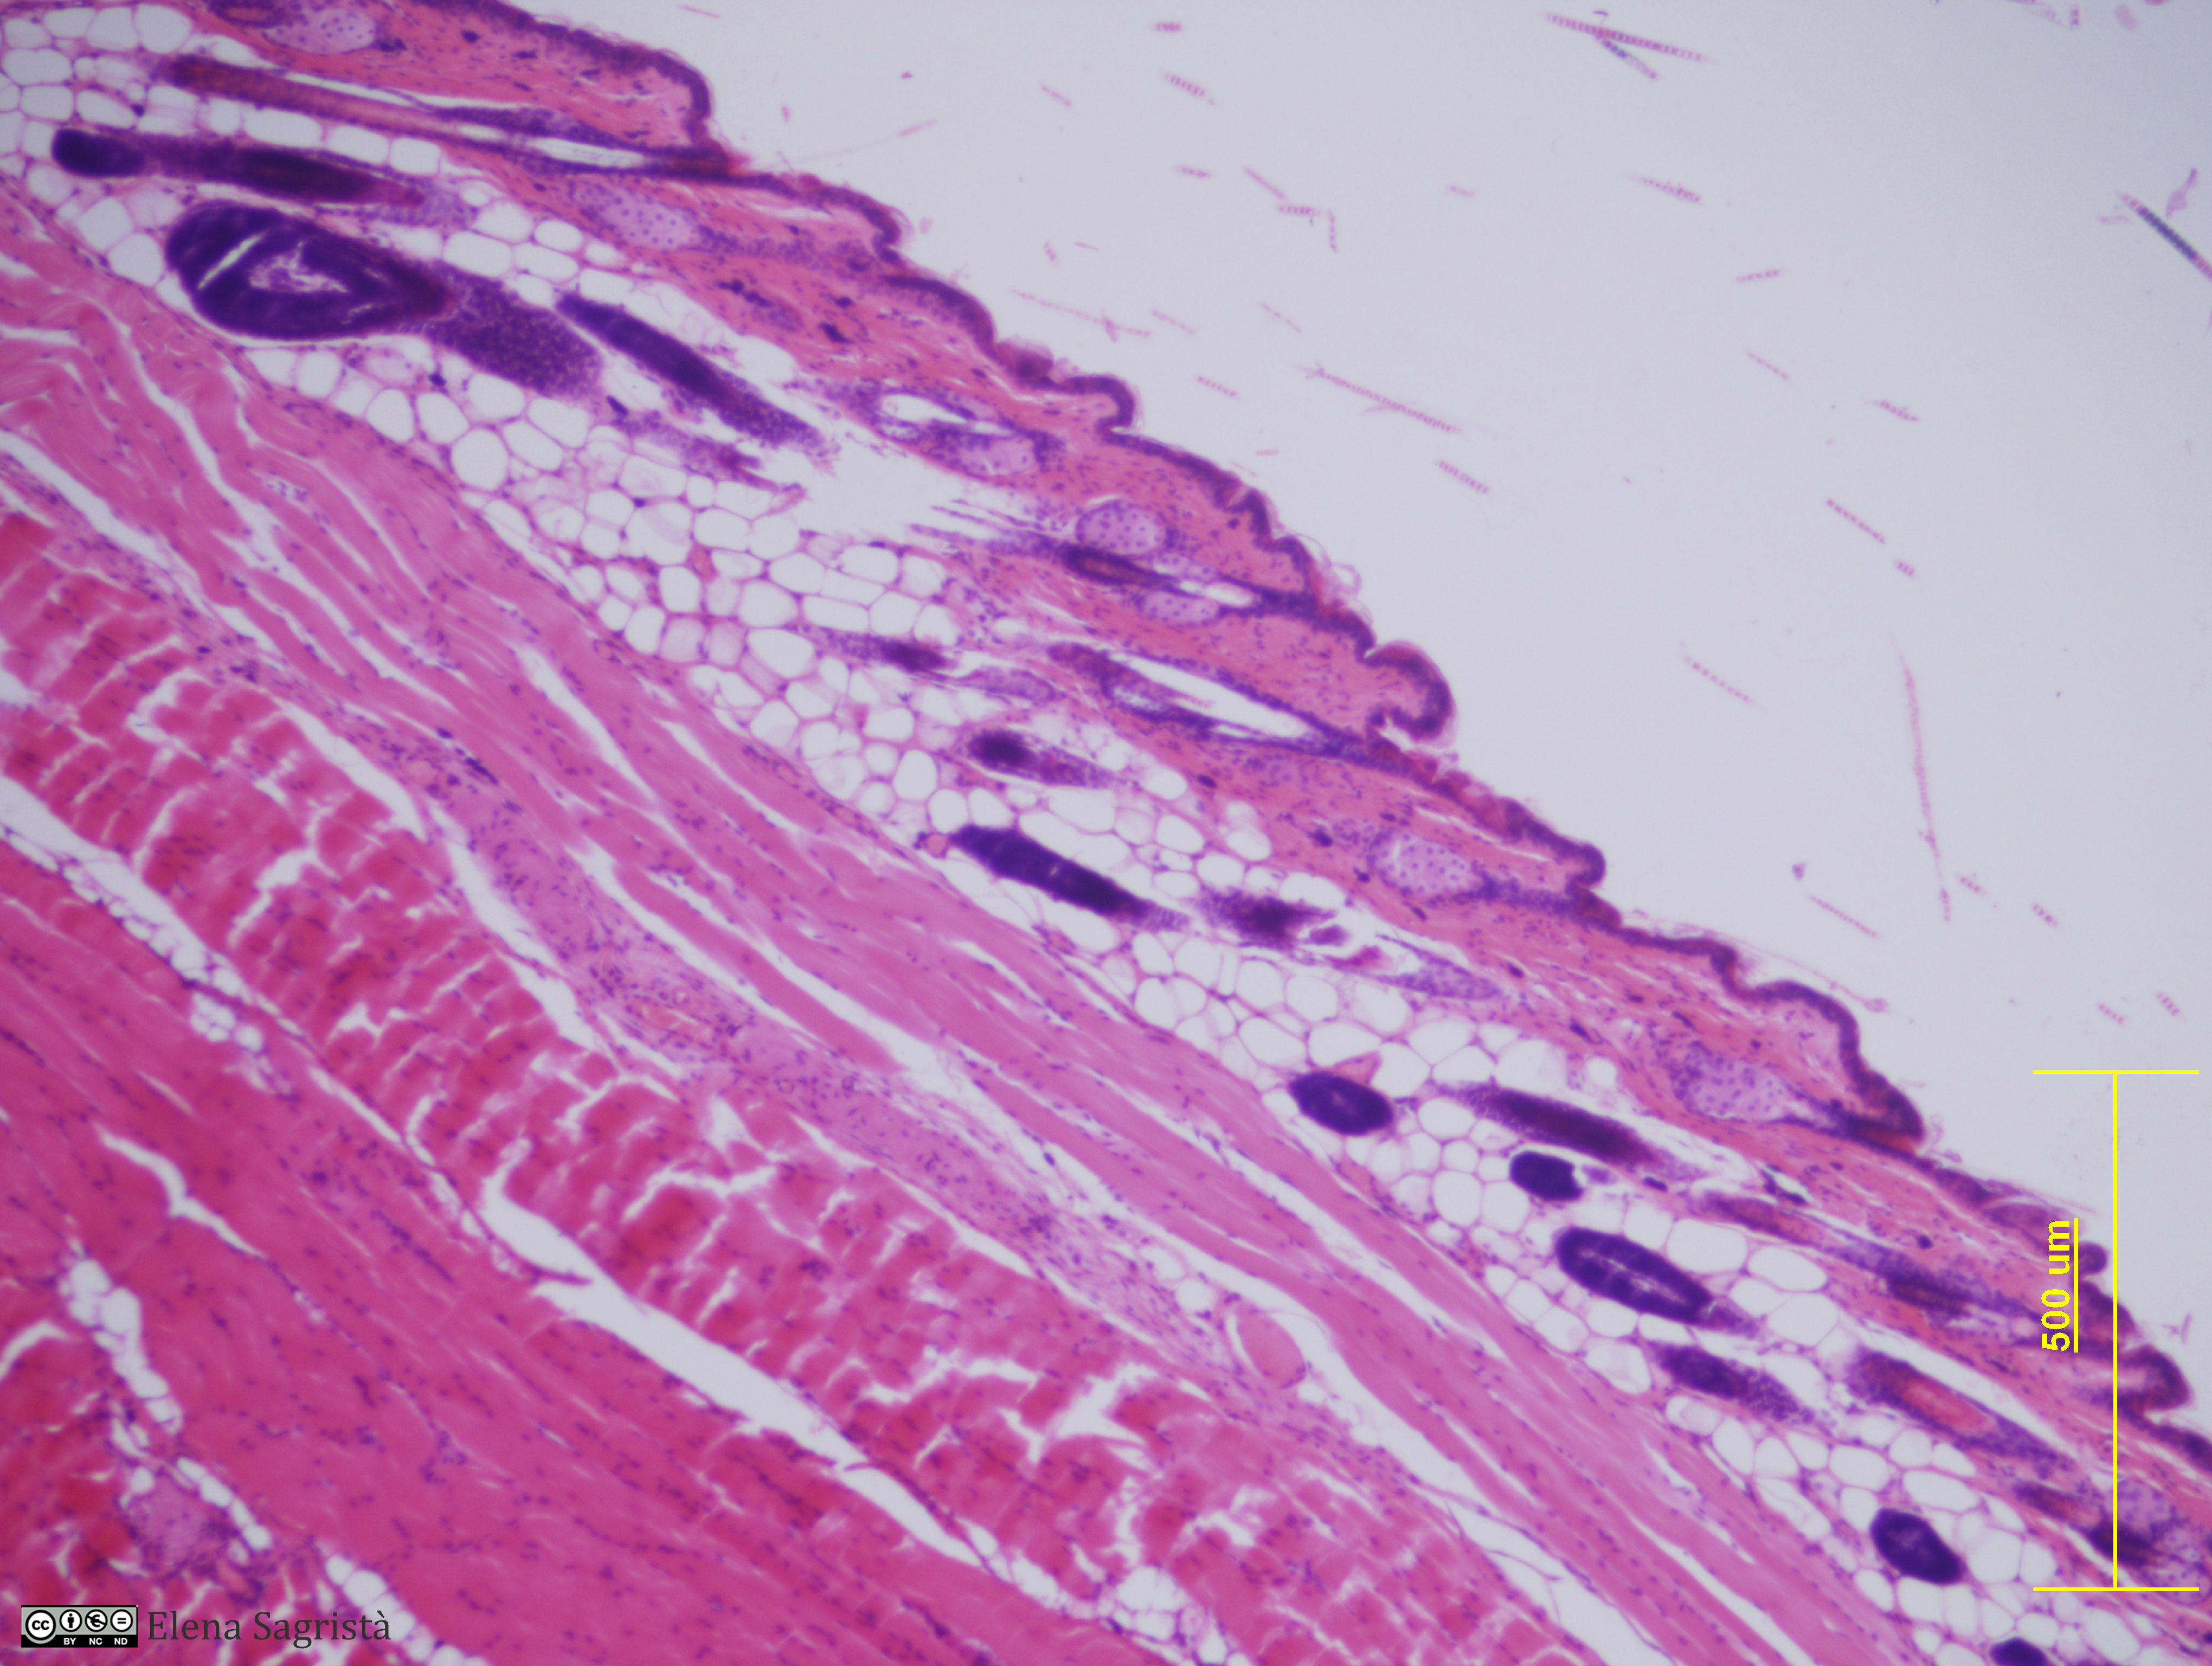

Histologia imatges: 11 Pell

Imatges de preparacions histològiques de Pell. Microscopia òptica.